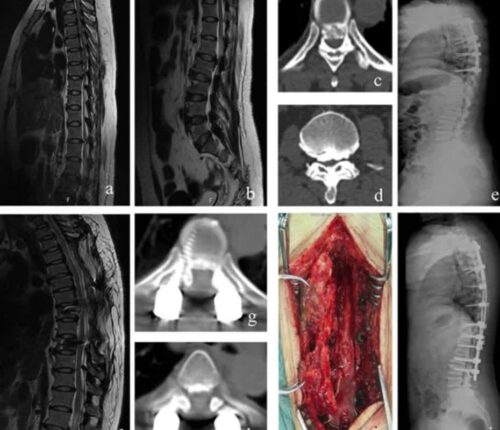

척추관 협착증 수술 증상 치료 5가지, 그 외에도 회복 재활을 위한 방법 공유